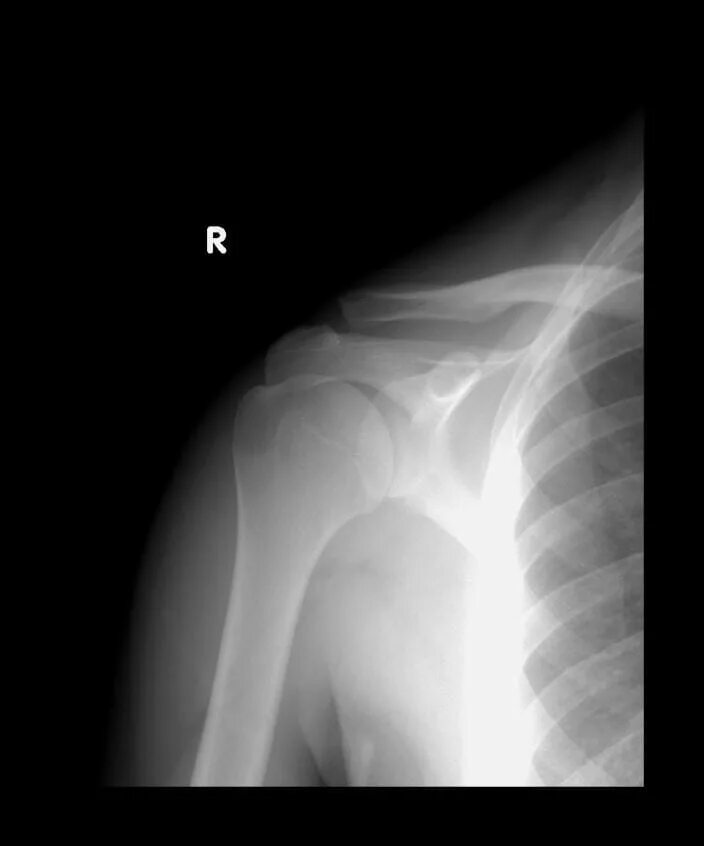

Деформирующий акромиально ключичного сочленения